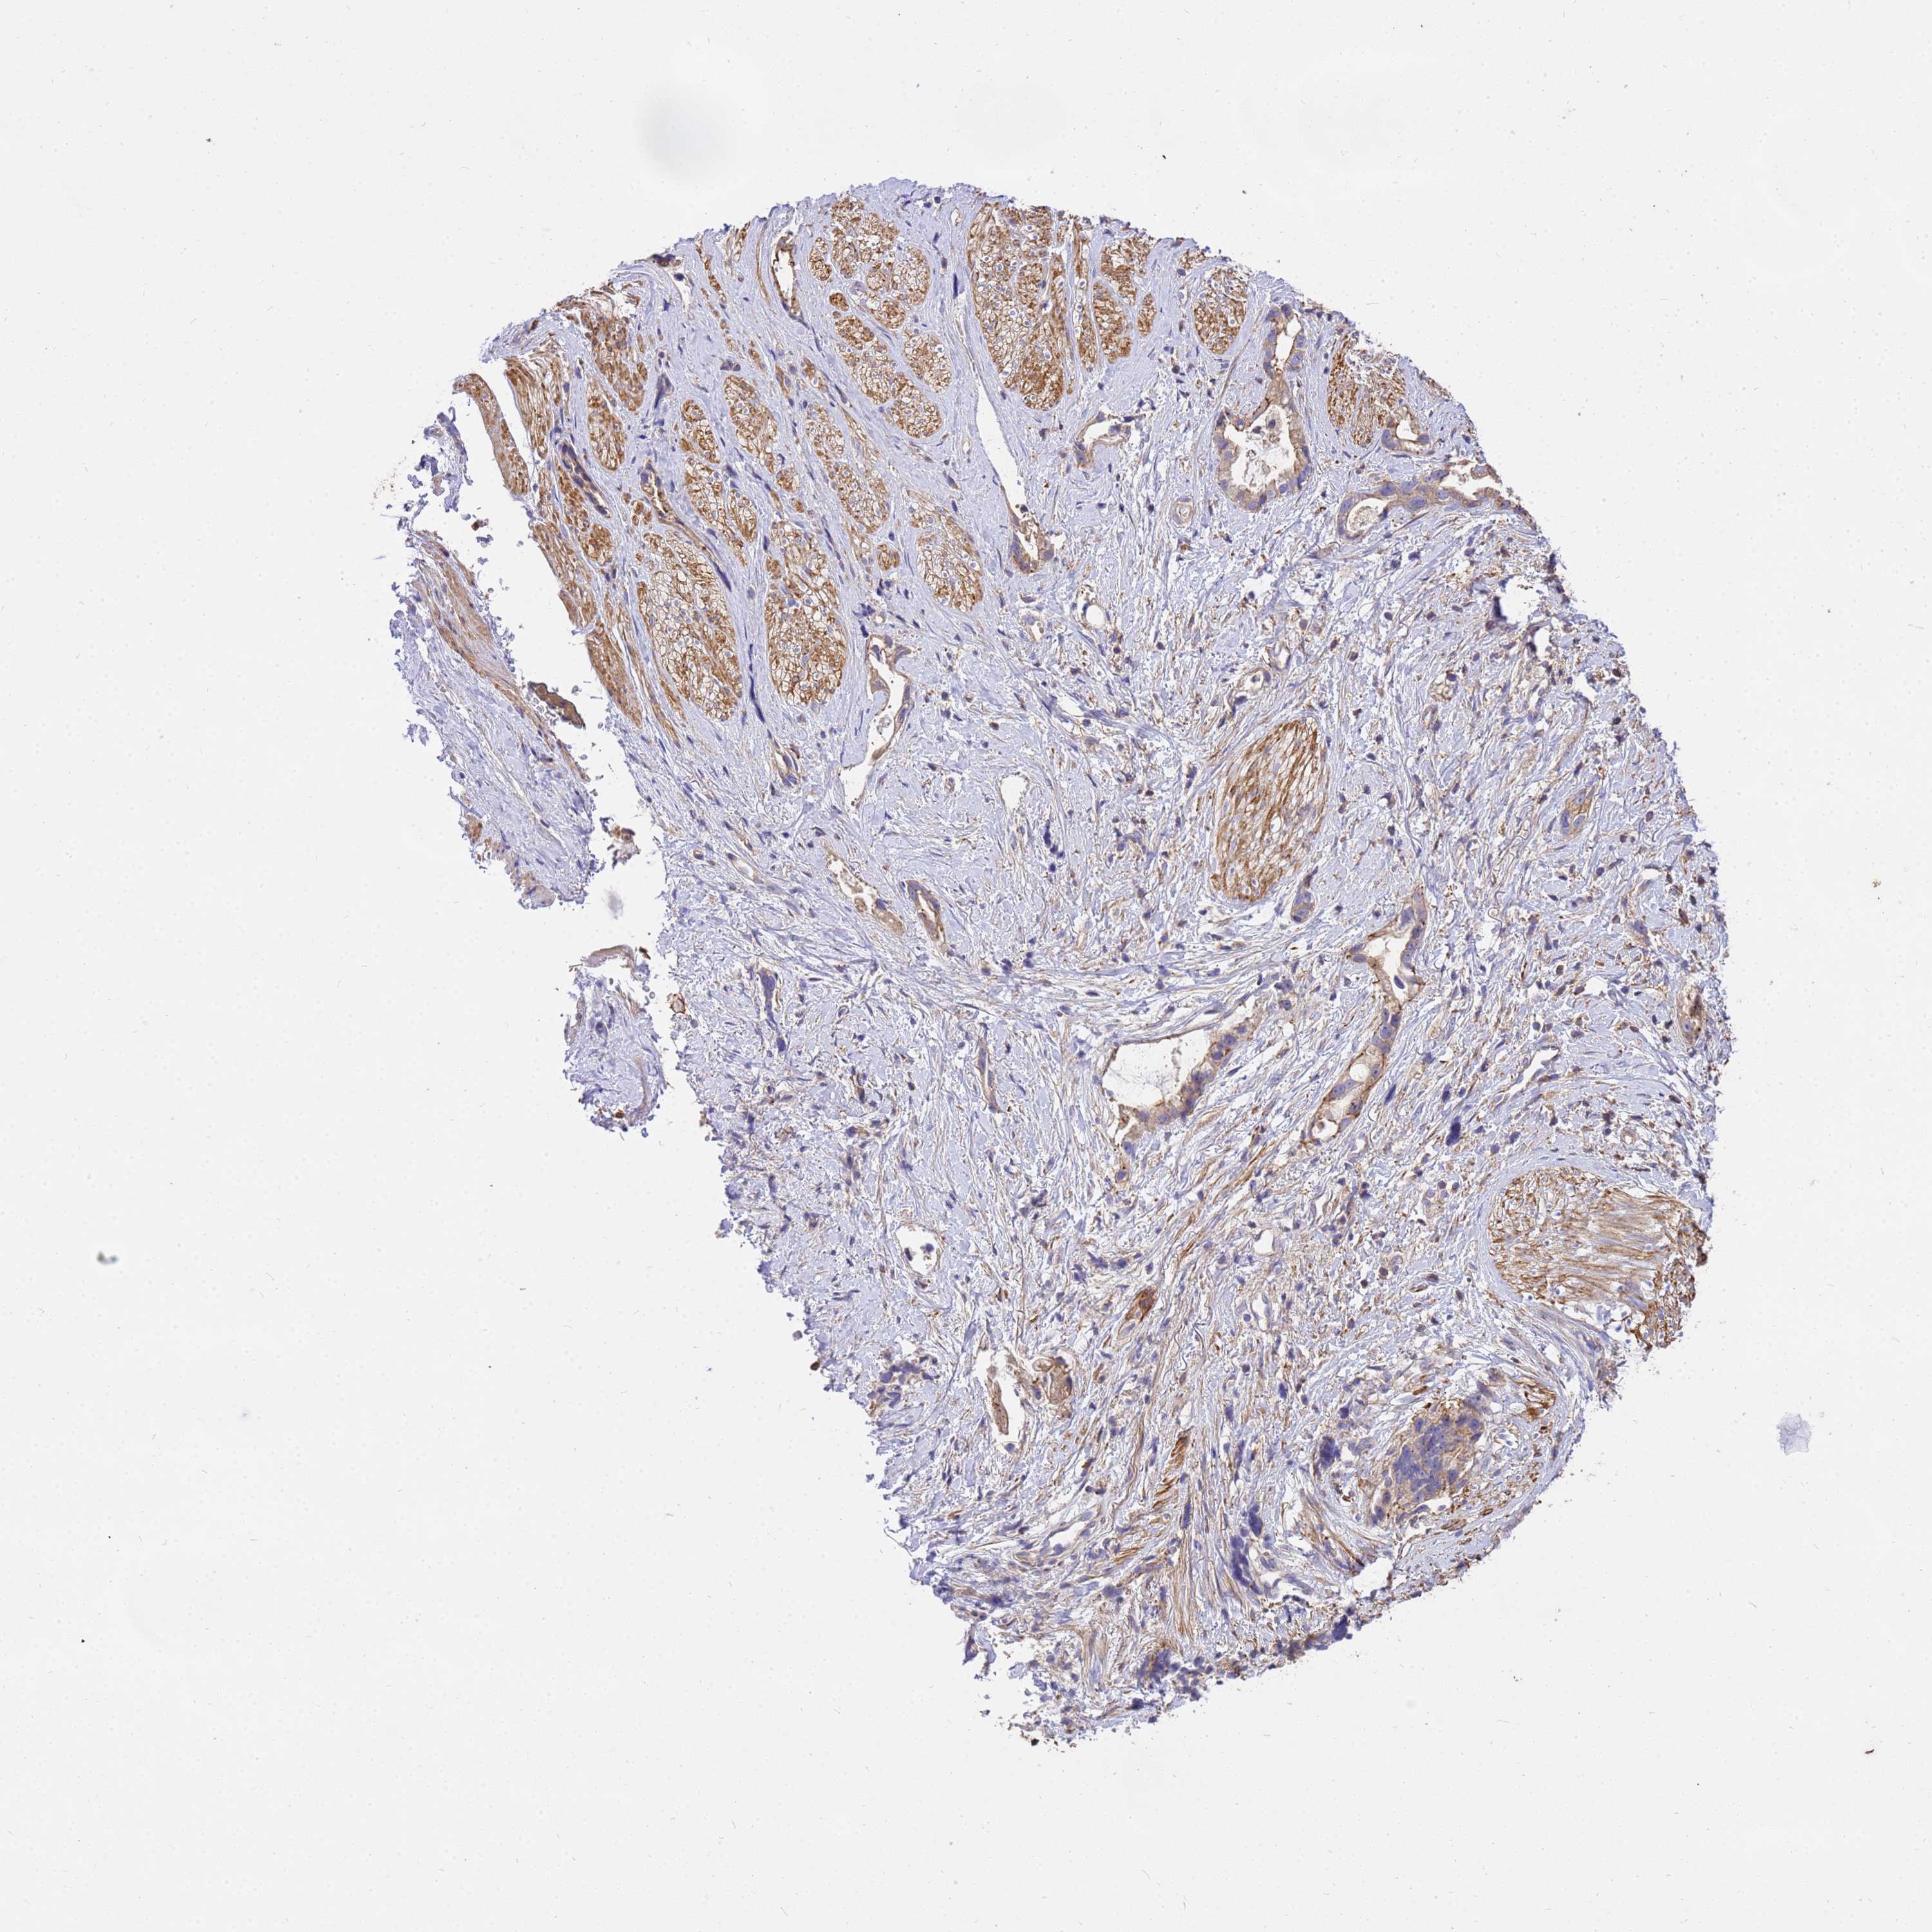

STOMACH CANCER - Protein expressioni

A mouse-over function shows sample information and annotation data. Click on an image to view it in a full screen mode. Samples can be filtered based on level of antibody staining by selecting one or several of the following categories: high, medium, low and not detected. The assay and annotation is described here.

Note that samples used for immunohistochemistry by the Human Protein Atlas do not correspond to samples in the TCGA dataset.

Antibody stainingi

Antibody staining in the annotated cell types in the current human tissue is reported as not detected, low, medium, or high, based on conventional immunohistochemistry profiling in selected tissues. This score is based on the combination of the staining intensity and fraction of stained cells.

Each image is clickable and will lead to virtual microscopy that enables deeper exploration of all samples and also displays staining intensity scores, fraction scores and subcellular localization as well as patient and tissue information for each sample.

Antibody HPA046186

Staining

High

Medium

Low

Not detected

Intensity

Strong

Moderate

Weak

Negative

Quantity

>75%

75%-25%

<25%

None

Location

Nuclear

Cytoplasmic/membranous

Cytoplasmic/membranous,nuclear

Adenocarcinoma, NOS